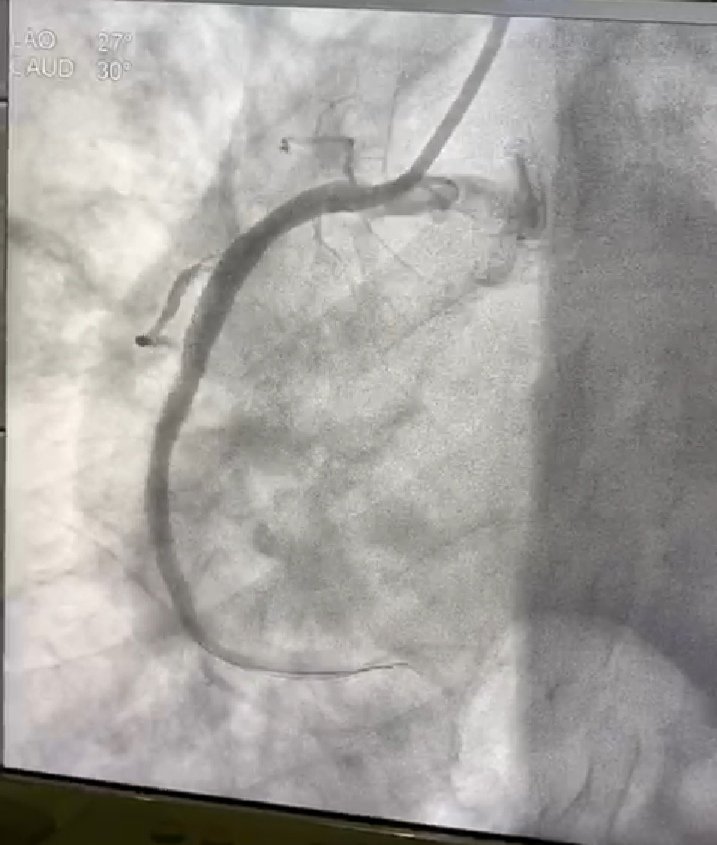

يسألنى الكثير عن ضيق الصمام الميترالي الناتج عن الحمه الروماتيزميه.. هو ضيق ناتج عن التهاب الصمام الميترالي نتيجة أصابه هذه الصمامات ببكتيريا معينه خلال الطفوله.ينتج عن الضيق كتمه فى النفس.العلاج أما جراحى او عن طريق القسطره اذا كان مناسب. هذه صور من مركزنا لعلاج مريضه بالقسطره.

ان برنامج علاج أمراض الصمام الميترالي عن طريق القسطره بمركز الملك فيصل لأمراض القلب بالحرس الوطني بجده يعتبر احد اهم المراكز فى تقديم هذا النوع من العلاج.. حيث يتم علاج ارتجاع الصمام او ضيق الصمام بالقسطره اذا كان مناسب.. هذه حاله توسيع الضيق باستخدام البالون عملنها بالامس.